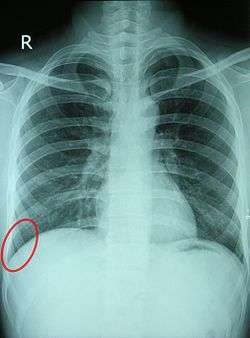

![]() Chest X-ray of a 30-year-old healthy man, with the costodiaphragmatic recess label in red ellipse | |

The costodiaphragmatic recess, also called the costophrenic recess or phrenicocostal sinus,[1] is a potential space in the pleural cavity, at the posterior-most tips of the cavity, located at the junction of the costal pleura and diaphragmatic pleura (in the costophrenic angle). It measures approximately 5 cm vertically and extends from the eighth to the tenth rib along the mid-axillary line.

In anatomy, the costophrenic angles are the places where the diaphragm (-phrenic) meets the ribs (costo-).

Each costophrenic angle can normally be seen as on chest x-ray as a sharply-pointed, downward indentation (dark) between each hemi-diaphragm (white) and the adjacent chest wall (white). A small portion of each lung normally reaches into the costophrenic angle. The normal angle usually measures thirty degrees.